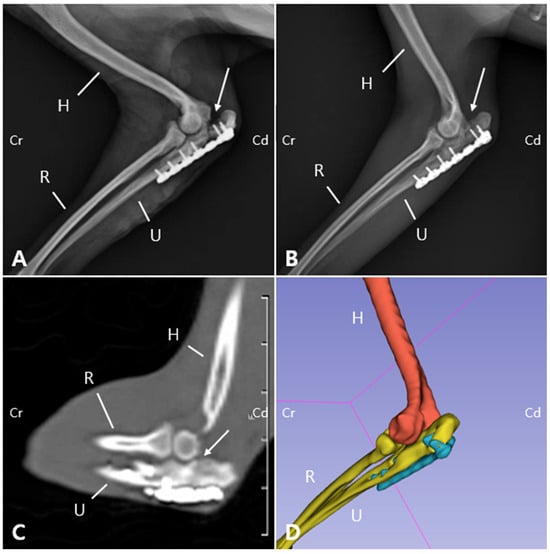

Two weeks postoperatively, the sutures were removed. Follow-up evaluations were subsequently performed including physical and orthopedic examination, gross gait analysis and radiography. The bandage was maintained for 30 days postoperatively as a means of coaptation to limit excessive joint motion, given the articular nature of the fracture and the associated ulnohumeral luxation. Although a transarticular external fixator could have been considered, this option was not pursued due to management challenges and financial limitations. By postoperative day (POD) 50, the patient was able to bear weight on the left forelimb during walking, with a lameness score of 3/5, although mild weight shifting was still observed [19]. Radiographs revealed a visible fracture line but reduced sharpness of the margin of the ulnar trochlear notch (Figure 5A). On postoperative radiographs, the anconeal process was not clearly identifiable, which was consistent with the gross appearance of 3D printed models (Figure 2 and Figure 5). On POD 140, the owner reported that the patient was fatigued easily during walks but was able to walk normally and showed satisfactory recovery. Gait evaluation performed at the hospital exhibited a lameness score of 0/5, with no observable lameness during walking or trotting [19]. Additionally, no pain response was elicited during palpating or passive range of motion the joint. The ROM of the left elbow joint improved to 40–140°, comparable to that of the right elbow joint (45–165°), and revealing significant improvement compared to the initial presentation (25–95°). These findings suggest that functional preservation of the joint was successfully achieved. Radiographs and CT images acquired at POD 140 confirmed progressive reduction of the fracture line gap (Figure 5B,C). Three-dimensional modeling reconstructed from CT data further demonstrated the stable positioning of the implants and restoration of anatomical alignment (Figure 5D). Follow-up information obtained from the owner confirmed that, as of 483 days postoperatively, the patient was doing well without any evidence of forelimb lameness.

Figure 5. Sequential radiographic and CT evaluation of fracture healing following plate fixation. (A) Medial view radiographs obtained on the day of surgery show appropriate plate placement with a clearly visible fracture line (arrow). (B) At 140 days postoperatively, the fracture gap appears reduced (arrow). (C) On the CT scan acquired at POD 140, the previously distinct fracture line is no longer discernible. (D) The 3D reconstruction generated from the CT dataset revealed the absence of the anconeal process. (H: Humerus; U: Ulna; R: Radius; Cr: Cranial; Cd: Caudal).